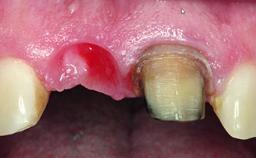

A healthy 37-year-old female patient was referred for a consultation on the replacement of missing tooth 21 with an implant-supported restoration. She stated that several years previously the tooth had been traumatically avulsed following a motor vehicle accident. The tooth was replaced with a three-unit fixed partial denture (FPD) immediately afterwards. Over time, she became disillusioned with the FPD and looked for a different option, including orthodontic therapy. She presented still in her orthodontic appliances, with the pontic sectioned free from the FPD but attached to the archwire. Her orthodontist felt that orthodontic treatment had been successfully completed, but nevertheless referred her before removing the appliances in case adjustments were necessary.

Defining Characteristics One missing tooth to be replaced by an implant-borne prosthesis

Placement Protocol Early or late implant placement

Bone Volume Deficient horizontally, allowing simultaneous augumentation

Esthetic Risk High